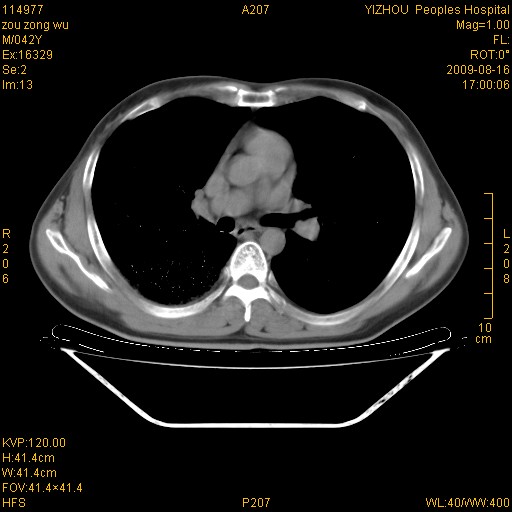

以下是引用zjzjr在2009-8-17 10:42:00的发言:[br]右侧间质性肺炎伴纤维化,右肺下叶肺囊肿伴感染(不除外外伤后引起),右肺野及胸壁软组织\\肝内见多发斑点状,中枪了吧.右侧胸膜肥厚\\粘连.